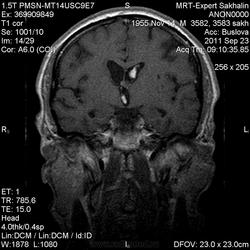

ID:53258

Онмк по геморрагичесому типу с образованием внутримозговой гематомы (подострая аза), прорывом в полость левого бокового и III -го желудочков.

Цель введения контраста наверное для исключения объема. Хотя. Наверное только динамика ответить на данный момент. Надо выносить в заключение весь диагностической ряд. Но больше похоже действительно на зона геморрагического НК. А сосуды не делали? Может имеет место венозное нарушение?

Танюша, не-а, в данном случае не имет место. Классика.

И почему острая фаза?Подострый период.

Да, подострый, не знаю куда я смотрел, что насчитал менее 3 дней.